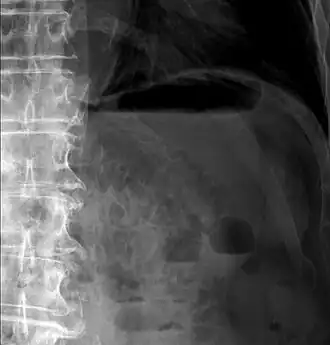

Pneumatosis intestinalis at computed tomography in intestinal ischemia. Lung window for better representation of the gas deposits in the intestinal walls. Coronal reconstruction. -

Upright AP radiograph showing gas in the wall of the small bowel in the left upper quadrant indicative of pneumatosis intestinalis.